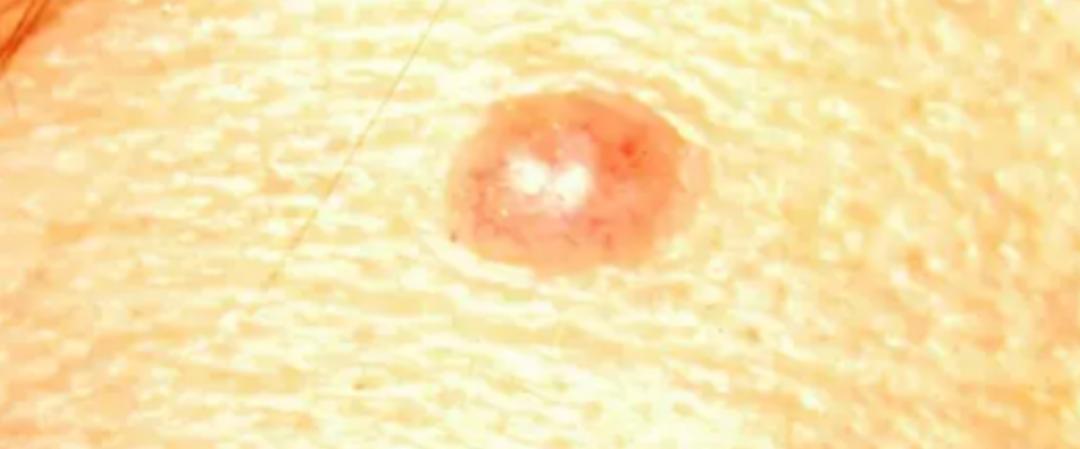

色素痣一般都是圆形或者椭圆形,比较对称;而黑色素瘤往往都不对称。

色素痣:

黑色素瘤:

C(Color)颜色

一个色素痣,颜色基本上都是均匀的,就是单一的颜色;但黑色素瘤的黑色往往不太均匀,颜色也可以是五颜六色,出现黑色、棕色、棕褐色等颜色,甚至还可以出现白色、灰色、红色和蓝色的区域。